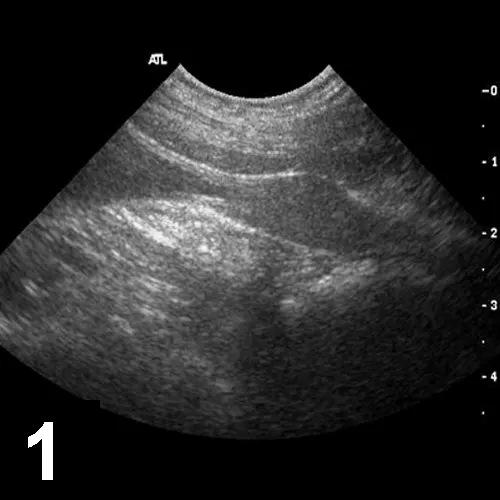

Abdominal ultrasonography—including both inguinal canals to the extent that was possible—disclosed no abnormalities, including presence of an abdominal testis. The prostate appeared enlarged and hyperechoic—typical of a mature male (Figures 1 and 2).

Figure 1. Sagittal image of a normal prostate in a castrated dog